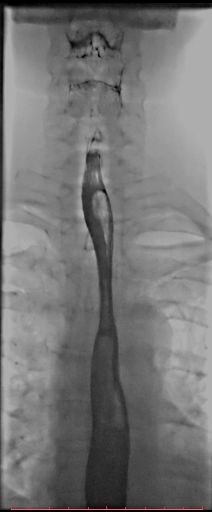

白色文字(排除指定关键词) Imaging Anatomy: interactive PACS-like atlas of radiological anatomy

解剖学模块